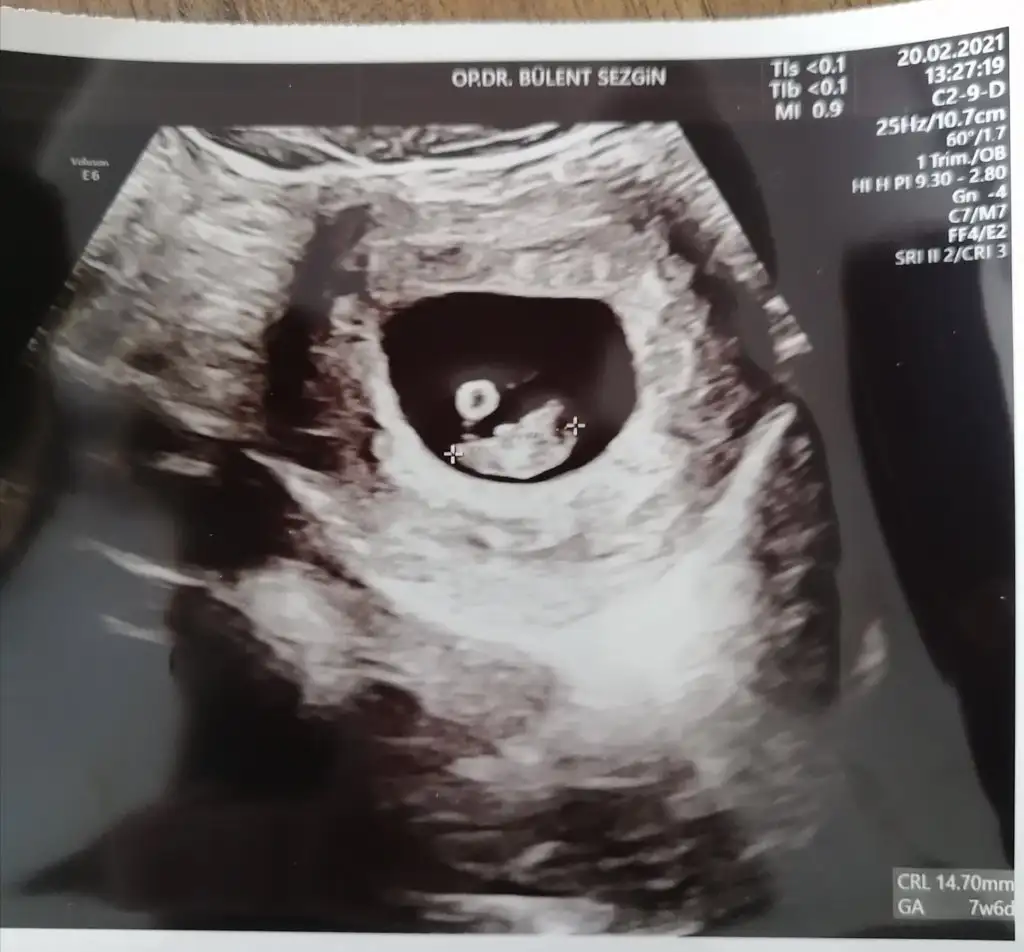

6+5 ve 7+6 acaba nedir çok merak ettim T Takitoki

• IMG_20210220_141159.webp

32,7 KB · Görüntüleme: 110

6+5 7+6 karından usg yazmayı unutmuşum tekrar attım T Takitoki

32,7 KB · Görüntüleme: 80